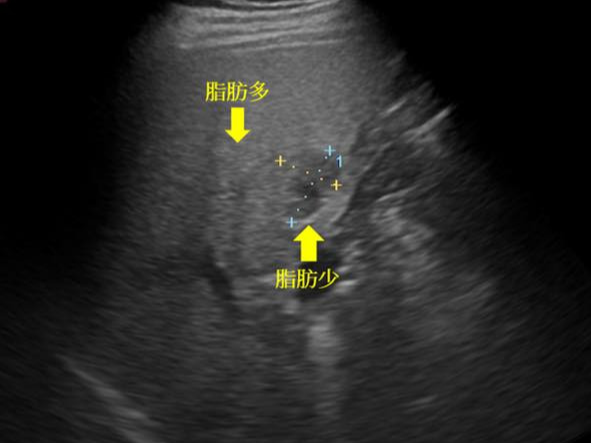

단점

• 장내 가스·비만 등의 경우 영상 선명도 저하

• 영상 해석이 검사자의 숙련도에 따라 차이 발생

• 공기나 뼈에 가려지면 정확도 제한

• 장기 외 구조(위장관 내부 등)는 제한적